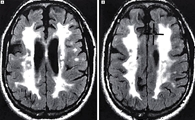

피질하 경색과 백질뇌증을 동반하는 상염색체 우성 뇌동맥질환(Cerebral Autosomal Dominant Arteriopathy with Subcortical Infarcts and Leukoencephalopathy)